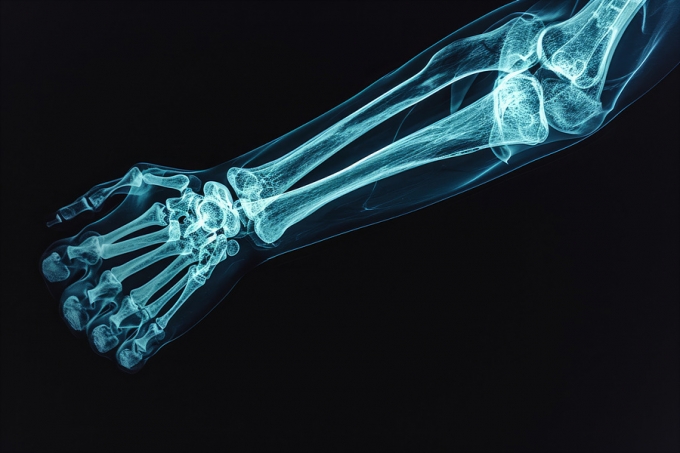

결과는 충격적이었다. PFAS 대표 물질인 과불화옥탄산(PFOA) 농도가 높은 청소년일수록 팔뚝 골밀도가 낮은 경향이 확인됐다. 일반적인 골밀도를 100으로 두면 PFOA 노출이 높을수록 골밀도가 98~92 수준까지 떨어지는 것으로 확인됐다. 연구팀은 "골밀도가 90만 되어도 골절 위험이 약 1.4배 증가한다"고 설명했다.

다른 PFAS 물질들도 노출 시기에 따라 영향이 달랐지만 성장기 뼈 발달에 영향을 미치는 것으로 파악됐다. 특히 성장 초기 등 특정 발달 단계일 때 영향이 더욱 크게 나타났다.

PFAS 노출과 골밀도 감소 간 연관성은 여아에게서 더 뚜렷하게 나타났다. 연구진은 성별에 따른 호르몬 변화나 성장 속도 차이가 영향을 미쳤을 가능성을 제기했다.